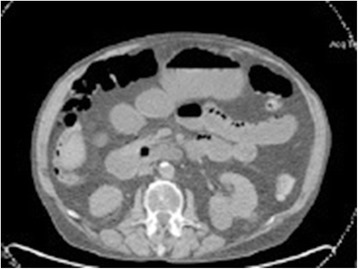

Figure 3.

CT scan of the abdomen. CT scan of the abdomen showing a distention of small bowel loops with several air-fluid levels.

A 62-year-old gentleman with chronic obstructive pulmonary disease (COPD) from chronic smoking presented with worsening cough and constipation for three months. Within the last year, the patient was recurrently treated for COPD exacerbations without significant clinical improvement. The patient denied having had fever, pain, nausea, vomiting, night sweats, or weight loss. Vital signs were unremarkable and pertinent findings on physical exam included mild wheezes on both lungs with decreased breath sounds over the left upper lobe, enlarged left supraclavicular lymph nodes, and hypoactive bowel sounds. Laboratory exams revealed a low sodium concentration of 130 mEq/L (normal 136–145 mEq/L), however other results were all within normal range. Computed tomography (CT) and positron emission tomography (PET) scans showed a large left upper lobe fludeoxyglucose (FDG)-avid mass (standardized uptake value (SUV) 14.3) and enlarged left supraclavicular lymph nodes with avid FDG uptake (SUV 4.0) (Figures 1 and 2). Brain magnetic resonance imaging (MRI) revealed no metastatic disease in the brain. Subsequent fine-needle aspiration of the left supraclavicular mass and immunohistochemistry staining confirmed small cell neuroendocrine cancer positive for thyroid transcription factor (TTF-1) and synaptophysin confirming the diagnosis of small cell lung cancer (SCLC). The disease was determined as extensive disease due to the fact that tumor/nodal volume was too large to be encompassed in a tolerable radiation plan. During the hospital course, the patient’s bowel movements further declined despite an aggressive bowel regimen. Ultimately, the patient developed symptoms akin to bowel obstruction and a CT scan revealed small bowel distention with multiple air-fluid levels (Figure 3). Considering possible mechanical bowel obstruction surgery was consulted and the patient underwent small bowel resection of the terminal ileum and cecum. However, no tumorous obstruction was found and histologic examination of the resected sample revealed intense lymphoplasmacytic infiltration consistent with myenteric ganglioneuritis as this is typically found in CIPO (Figure 4). Anti-Hu antibodies were positive with a titer of 1:640. Collectively, the laboratory and pathologic findings were consistent with paraneoplastic CIPO with underlying SCLC.